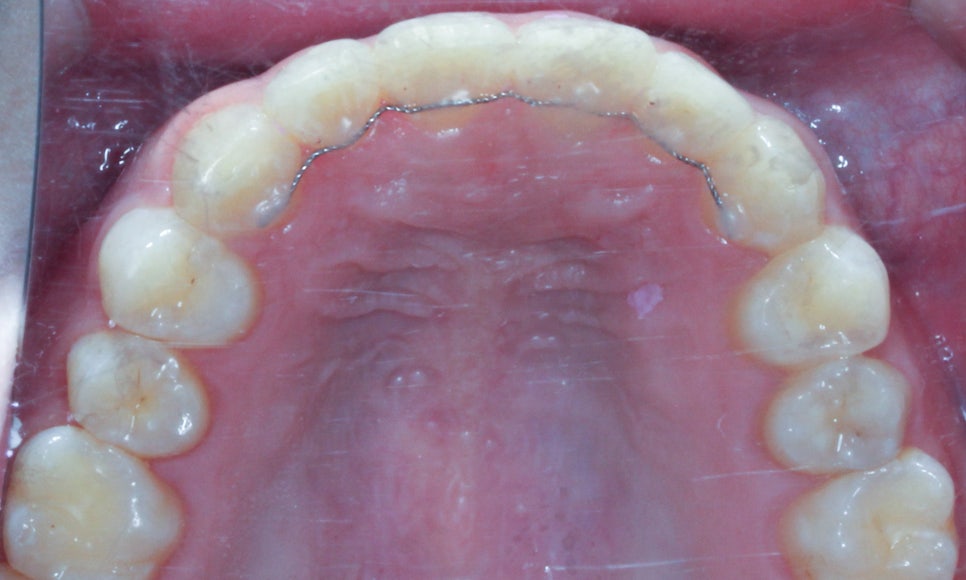

상악과 하악의 안쪽면 사진에서도

치아의 총생이 발견되었습니다.

상악의 경우 앞니의 나비치아 성향이 두드러지는 반면

하악의 경우에는 중절치의 미세한 돌출과

측절치의 이탈로 인해 총생이 발견되네요.